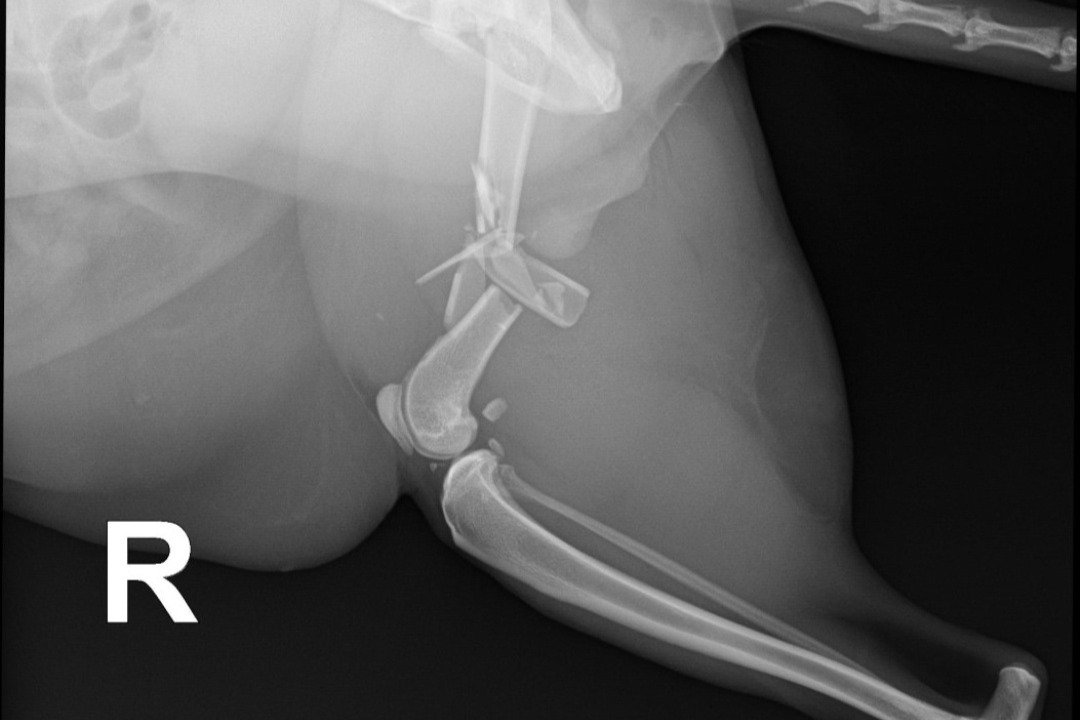

*Romeo's X-Rays*Our 4 year old cat Romeo has been SEVERELY injured and the vet stated that she believes he was crushed. When we came home after bringing him to the hospital, we realized that our boxspring was broken, so we believe that it fell onto him and crushed him. He has broken ribs, a shattered femur, etc. He will need to have his leg amputated, which in itself is $7000 and would be $17,000 if we decided to keep the leg and have them try to fix it and we genuinely cannot afford it.. And those prices are for his leg alone, it doesn't include the cost for his ribs or medications, or the $2000 a night to stay at the hospital. Please help us save our boy.. We cannot live in a world without him.. He's the most special cat in the entire world and our hearts are breaking. If we cannot afford the surgeries, then we will have to put him down. Please help in any way you can..